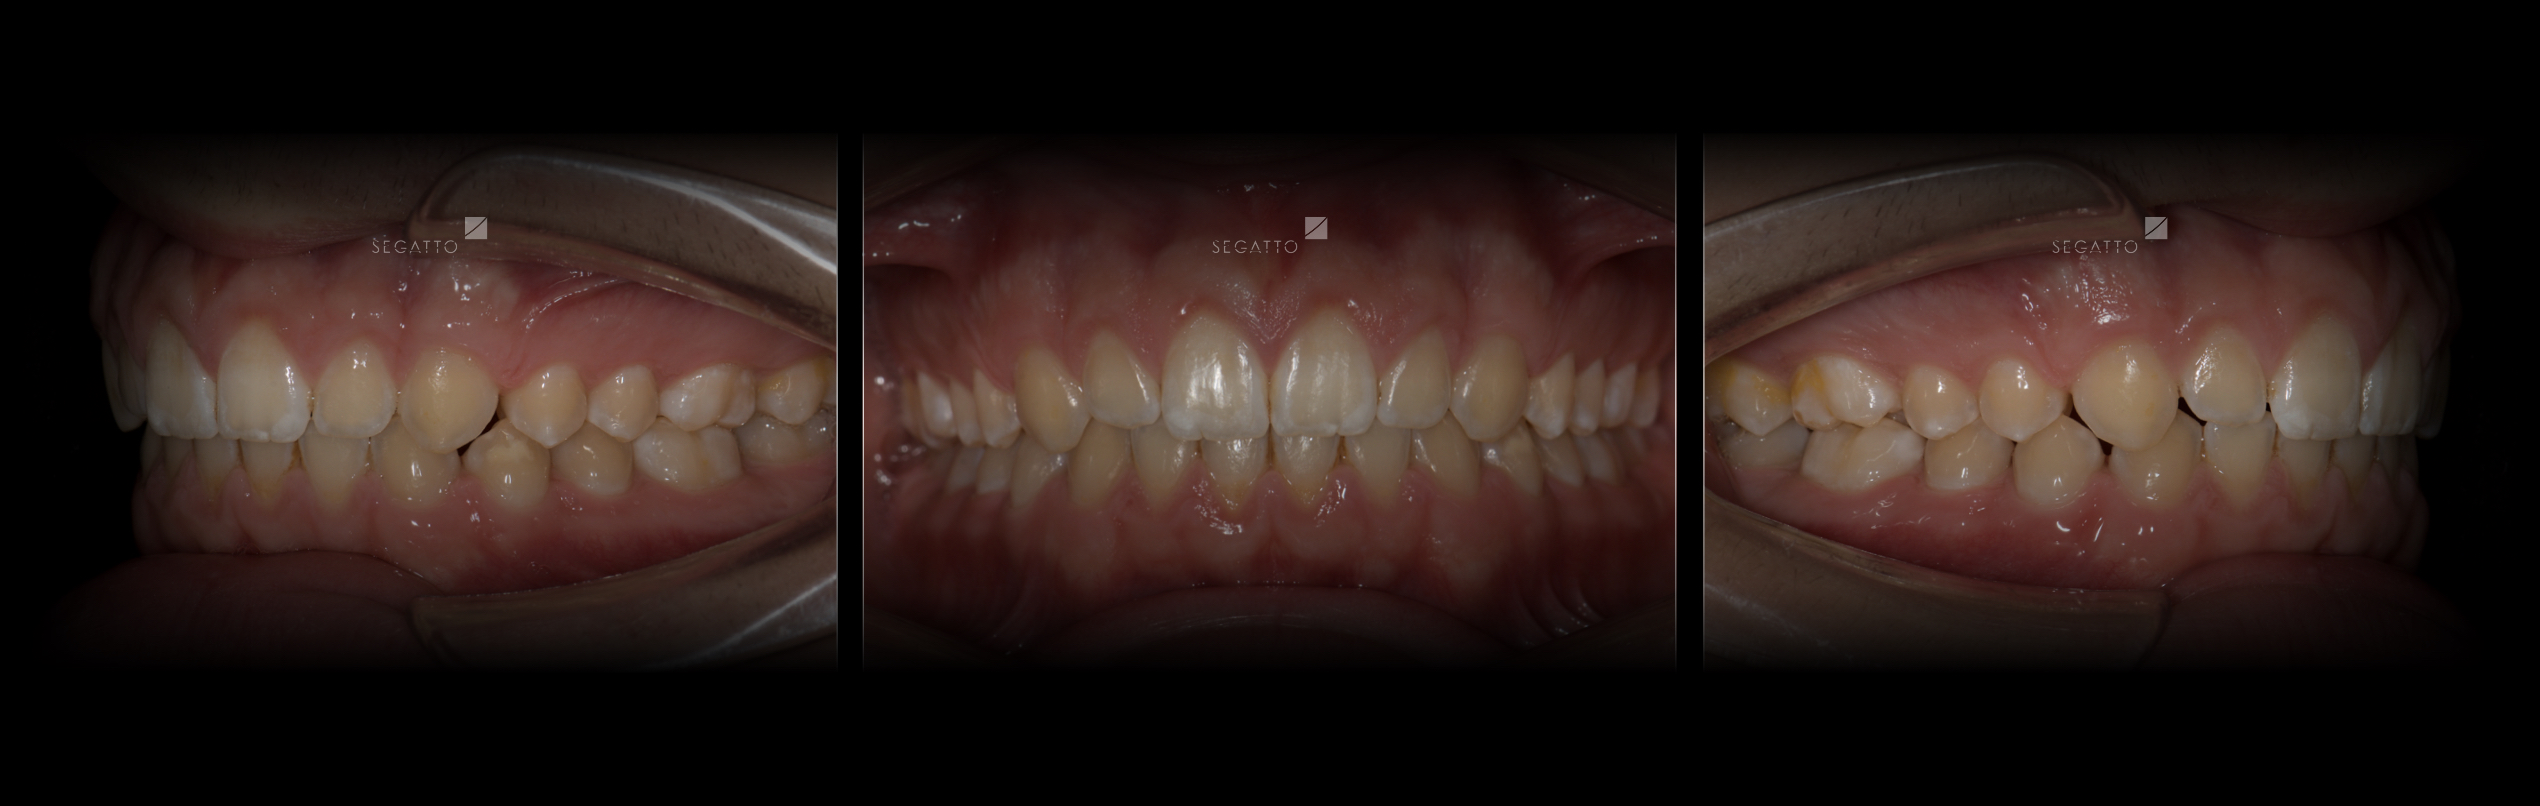

Orthodontics

Cases